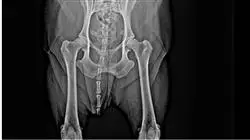

La frattura del bacino è caratterizzata dal coinvolgimento di più di un osso della zona pelvica o di strutture connesse ad essa, ciò comporta l’elevata esigenza di professionisti che possiedano un’ampia e dettagliata conoscenza dell’anatomia e della biomeccanica della zona pelvica negli animali, così da poter garantire un esito terapeutico ottimale in ogni paziente.

Risulta fondamentale conoscere le alterazioni fisiopatologiche che possono verificarsi in pazienti con frattura pelvica, poiché la maggior parte di queste è associata a forti traumi, come incidenti stradali o cadute da altezze elevate.

In considerazione di ciò e dei rapporti anatomici del bacino, questo programma spiega quali tipologie di lesioni si possono trovare associate a queste fratture (danni alle strutture neurologiche, lesioni agli organi addominali e alla parete addominale, ecc.), così come in altre regioni distanti dal bacino (lesioni toraciche o traumi cranio-cerebrali, per esempio), al fine di offrire un’assistenza terapeutica completa al nostro paziente.

Dal punto di vista terapeutico, sono state descritte molteplici opzioni per il trattamento delle fratture pelviche, che vanno dal trattamento conservativo alla terapia chirurgica con perni, viti, piastre e fissatori esterni. Per questo motivo, il traumatologo veterinario deve essere adeguatamente preparato nelle varie opzioni e raccomandazioni per ogni caso, al fine di scegliere il trattamento più appropriato in base alla presentazione clinica.